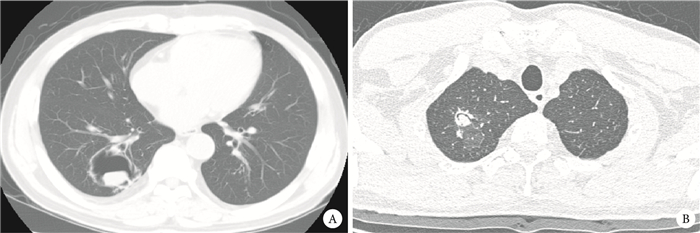

注:A為右肺內可見薄壁空洞影,其內可見孤立結節,可見“空氣半月征”;B為右肺內結節影,“空氣半月征”欠典型,術后病理證實為曲霉菌球形成

回顧性分析2009年6月至2014年5月首都醫科大學附屬北京朝陽醫院胸外科手術治療的肺曲霉菌球患者39例的臨床資料。本組首發癥狀為咯血者27例,主要表現為痰中帶血或咯少量鮮血,但其中19例為反復多次咯血。患者術前均接受胸部薄層高分辨率CT檢查(圖 1),明確病變范圍,術前影像學均考慮為肺部良性結節,病變大小約為3~6 cm。術前行纖維支氣管鏡檢查+活檢明確為曲霉菌球感染者7例,其余均經術后病理證實為肺曲霉菌球。咯血患者術前均行氣管鏡檢查,以便確認出血位置與影像學病變位置一致。按照手術方式不同將患者分為兩組:傳統開胸手術組11例,男8例、女3例,年齡29~64(50.7±9.7)歲;病變位于右肺上葉3例,左肺上葉3例,左肺下葉1例,跨葉4例(右中上葉1例,右中下葉2例,左下葉及舌葉1例)。術式包括肺局部切除術1例,肺葉及復合肺葉切除術10例;胸腔鏡手術組28例,男13例、女15例,平均年齡20~75(55.4±15.3)歲;病變位于右肺上葉8例,右肺中葉1例,右肺下葉4例,左肺上葉6例,左肺下葉6例,跨葉3例(右中下葉1例;左下葉及舌葉2例)。術式包括肺局部切除術9例,肺葉及復合肺葉切除術19例,胸腔鏡組無中轉開胸(表 1)。